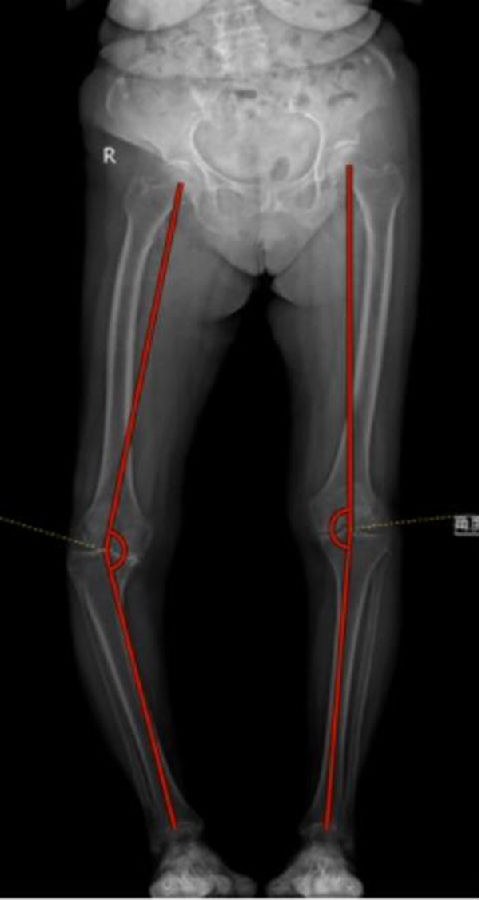

三、典型病例

一期双侧内翻膝aMA+arKA典型病例一例。王x,女性,80岁,因“双膝疼痛10余年,加重3月”入院。

PE:双膝内翻畸形,左膝稍肿胀,左膝活动度屈曲100°,伸直0°,内侧关节间隙压痛(+),浮髌试验(-),右膝稍肿胀,活动度屈曲100°,伸直0°,内侧关节间隙压痛(+),浮髌试验(-),双下肢皮肤感觉及末梢血运正常。

手术方案:左侧aMA,右侧arKA

图6图7 术前

图8 术前影像(R)